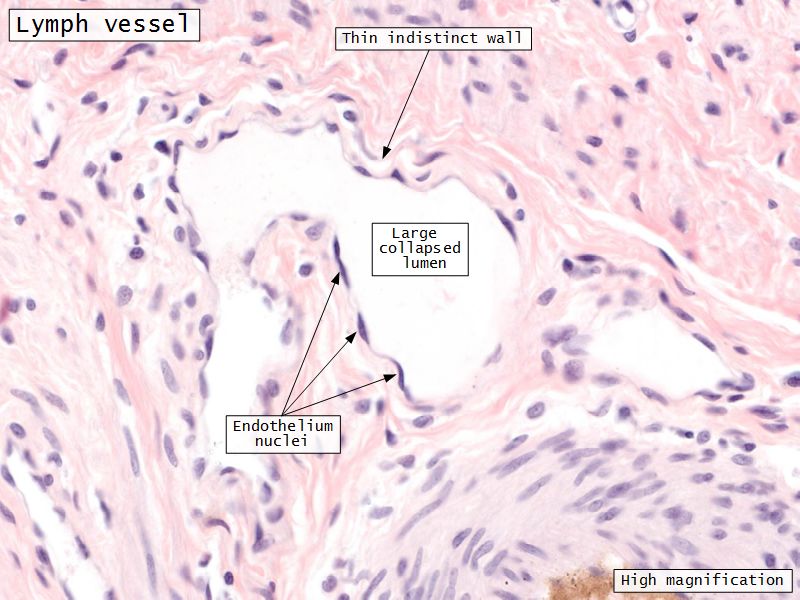

- Blood vessels

- Lymphatics